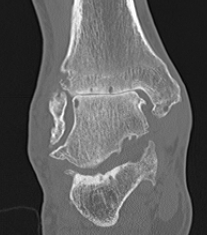

CT

Evaluate bone stock to determine if TAR is appropriate